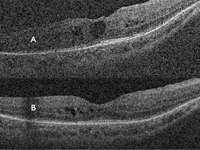

En la

Figura 2 se muestra un paciente con síndrome de Usher: en el recuadro verde (imagen superior derecha), la fóvea presenta una anatomía conservada, pero inmediatamente fuera de ella, en el recuadro rojo, se observa una pérdida de la anatomía normal a expensas de las cuatro capas externas, con atrofia del EPR. En la parte inferior de la composición se ofrece una imagen completa de la DRI-OCT.

Figura 2. DRI-OCT patológica. Paciente con síndrome de Usher. Imagen superior izquierda: retinografía de fondo de ojo del paciente. Imagen superior derecha: DRI-OCT foveal; en el recuadro verde, ampliación de la fóvea, con anatomía conservada; inmediatamente fuera de ella, en el recuadro rojo, pérdida de la anatomía normal a expensas de las cuatro capas externas con atrofia del EPR. Imagen inferior de la composición: DRI-OCT completa en la que se ven tanto el nervio óptico como la mácula.

Fijándose en el espesor de la coroides en la imagen de DRI-OCT de este paciente (

Figura 2, imagen inferior) y comparándola con la siguiente imagen de un voluntario sano (

Figura 3), puede observarse una disminución en el espesor.

Figura 3. DRI-OCT macular en voluntario sano: puede observarse un mayor espesor de la coroides comparando con la DRI-OCT del paciente con distrofia retiniana de la Figura 2.